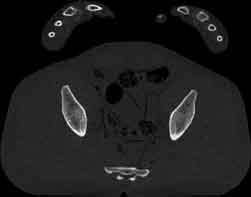

Visible Human male: Sectio transversalis 1838

CT

NMR

Pd                          / T2 \                         T1